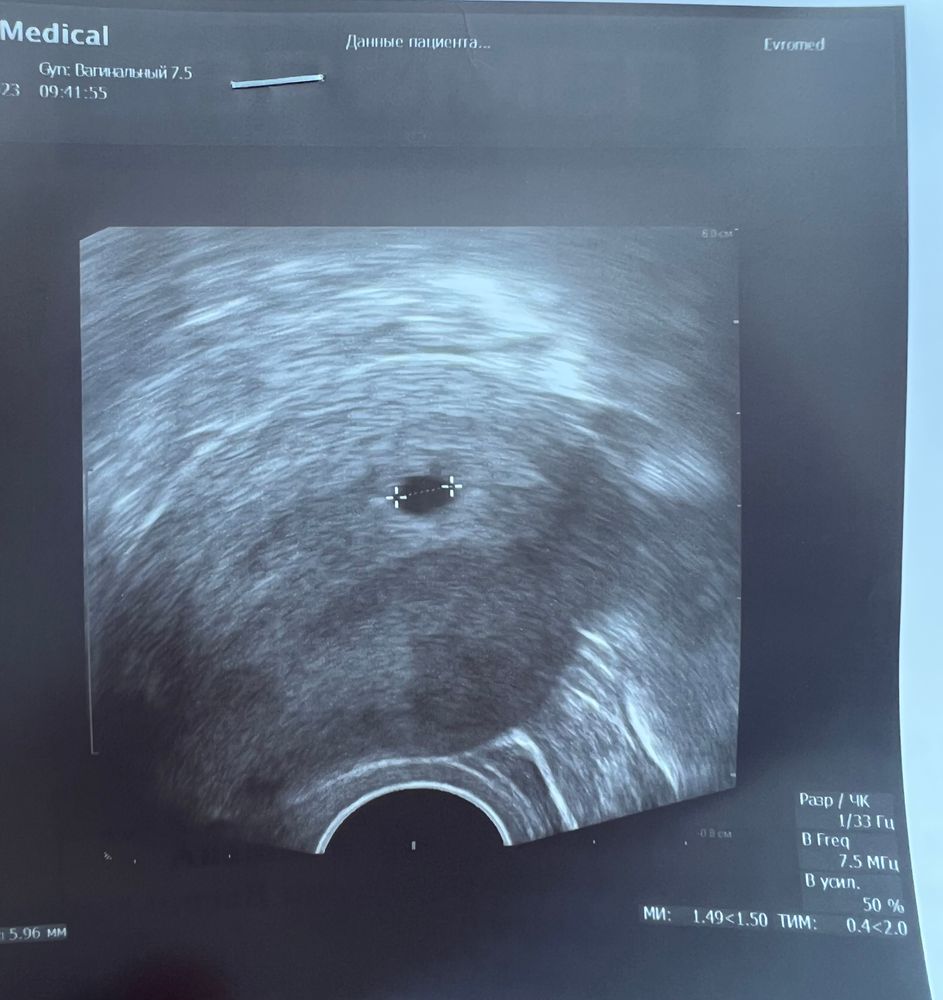

21 дпп узи

21 дпп узи 118 фото